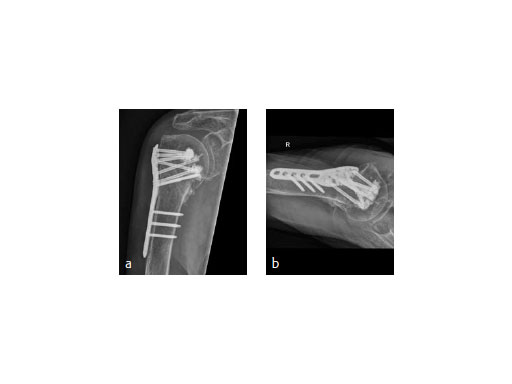

The patient was placed in supine position, having the shoulder on two shoulder supports. After closed reduction of the shoulder, ORIF was performed via an anterior deltopectoral approach using the PHILOS. Four screws were augmented with Traumacem V+ under fluoroscopic control. Initially the treated shoulder was immobilized in a sling for 2 days followed by a pain-adapted functional treatment (Fig 6).

The X-ray review at 3 months after surgery showed an anatomic reduction of the fracture, nicely formatted augmentation, no secondary loss of reduction, and range of motion of the arm reaching the horizontal plane (Fig 7).